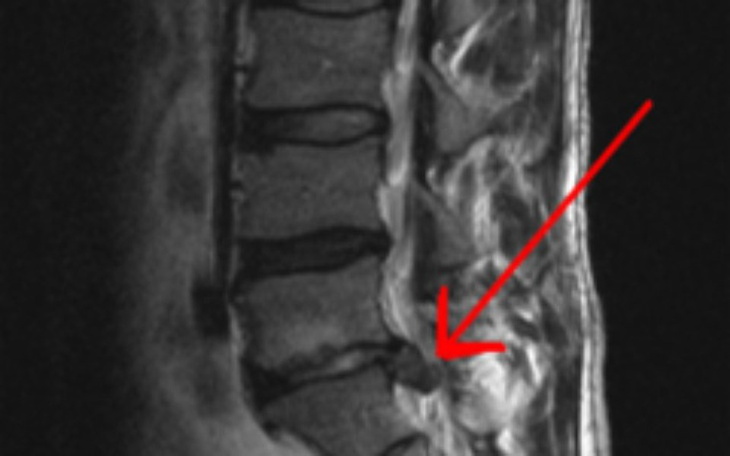

Zbieram pieniążki na operację kregosłupa mojego męża. Mój mąż jest jedynym zywicielem rodziny od jakiegos czasu ma problemy z kręgosłupem i niestety jak się okazało ma przepukline na kregoslupie . Koszt operacji w prywatnym szpitalu to 10 tysięcy a w państwowym szpitalu trzeba czekać półtorej roku niestety :( bardzo dziękuję za pomoc .